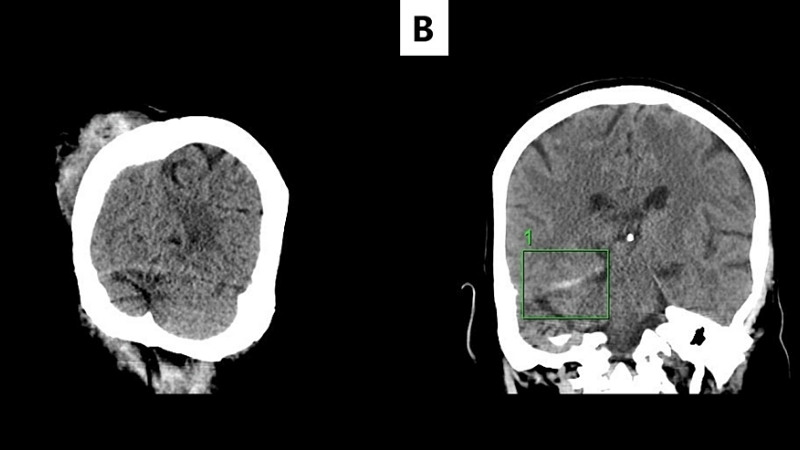

Image description of Herpes Simplex Encephalitis

Herpes Simplex Encephalitis is a rare but serious brain infection caused by herpes simplex virus. It leads to fever, headache, confusion, seizures, and potential long-term neurological damage. Early detection and treatment are crucial for recovery.

Encephalitis diagnosis needs MRI and lab tests